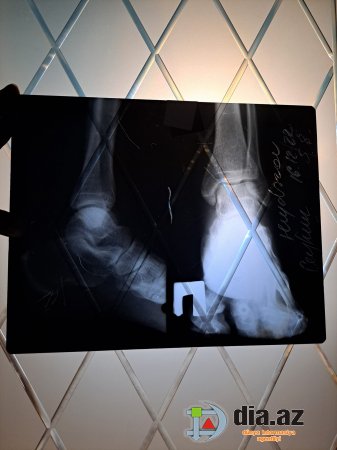

DİA.AZ: - "Şikayətim Elmi-Tədqiqat Travmatologiya və Ortopediya İnstitutunda qeyri-rəsmi çalışan rezident Ağa Mirməhəmməd Mirhaşım oğlundandır. 16.12.2022-ci il, 21:30 radələrində yoldaşım Ceyhun Heydərov avtomobil qəzası keçirmiş elə həmin gün Travmatologiya İnstitutuna müraciət etmişdir. İlkin baxış və rentgen müayinələrindən sonra özünü həkim kimi təqdim edən Ağa Mirməhəmməd rentgen nəticələrini düzgün oxuya bilməmiş və yoldaşımı arxayın edərək heç bir sınıq olmadığını, əzilmə və sıyrıq olduğunu demiş, xəstəni evə yola salmışdır". DİA.AZ bildirir ki, bu sözlər şikayətçi Gülyaz Əbilova-Heydərovanın müraciətində yer alıb. Narazı vətəndaş daha sonra bildirir: "Bir neçə gün sonra ayağın göyərdiyini və şişdiyini gördüyümüz üçün yenidən Travmatologiya İnstitutuna müraciət etmişik. Bu dəfə bir digər həkim travmatoloq 16.12.2022-ci ildə çəkilmiş elə həmin rentgen nəticələrinə baxaraq ayağın topuq nahiyəsində sınıq olduğunu aşkar etmiş. Təkrar KT müayinəsi etdirmiş və sınıq olduğunu tam dəqiqliklə təsdiqləmişdir. (Eyni zamanda tam əmin olmaq üçün özəl klinikalardan birinə də müraciət etmişik) Sınıq ilk gün Ağa Mirməhəmməd tərəfindən aşkarlanmadığı və dəqiq diaqnoz qoyulmadığı üçün sınıq yerdəyişmiş və nəticədə yoldaşım Ceyhun Heydərov 30.12.2022-ci ildə əməliyyat keçirmişdir. Əməliyyatdan bir neçə gün sonra Ceyhun Heydərov çox sakit və təmkinli bir şəkildə həmin şəxslə əlaqə saxlayıb, etdiyi səhvin nəticələrini özünə bildirmək istəyərkən şəxs-Ağa Mirməhəmməd Mirhaşım oğlu həkim peşəsinə və insanlığa sığmayan ifadələr işlədərək xəstəni təhqir edir, hədələyir, videodan da gördüyünüz kimi kriminal avtoritet kimi danışır, xəstəni və yaxınlarını "görüş"ə dəvət edir. Zərərçəkmişə "Sənin əməliyyat olunmuş ayağını sındıraram (gerisini ifadə etməyə tərbiyəm yol vermir)" deyir. Ailə böyüklərimiz onunla əlaqə saxlamaq istəyərkən yenə eyni tərzdə hədə-qorxu gəlir, asıb-kəsməklə hədələyir. Qeyd edim ki, yoldaşım Tip 2 Diabet olduğunu üçün əməliyyat və sonrakı proses çox çətin və həyəcanlı keçdi. Əgər həmin gün doğru diaqnoz qoyulsa zərərçəkmiş əməliyyat olunmayacaqdı. Hələ də xəstə sağalmayıb. Bu insan isə etdiyi səhvi etiraf edib üzrxahlıq etməksəndə, küçə ifadələri işlədir. Bu şəxs hal-hazırda International Medical Center klinikasında travmatoloq-ortoped kimi çalışır. Diqqətli olun və tanıyın. Yazdığı tövsiyə vərəqəsində isə nə adını doğru qeyd edib nə də nömrəsi var. Qeyd edim ki, bu haqda Elmi-Tədqiqat Travmatologiya və Ortopediya İnstitutunun rəhbərliyinə və Azərbaycan Respublikası Səhiyyə Nazirliyinə yazılı şəkildə rəsmi müraciət etsək də hələ heç bir nəticə əldə edə bilməmişik".